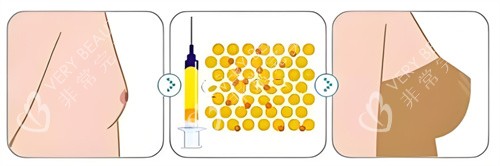

他自创的“脂肪三维护活体系”,从提取、提纯到填充全程把控:取脂时用2.0mm超细钝针,配合“扇形低负压抽取”,减少脂肪细胞破损;提纯时采用“离心+过滤+静置”三重处理,去除油脂、血水等杂质,保留活性高的脂肪颗粒;

填充时用“多点、分层、微量”注射法,将脂肪均匀注入乳腺后间隙和皮下层,避免堆积形成结节,不少求美者反馈术后3个月成活率高,基本一次就能达到理想罩杯。